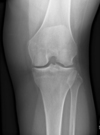

A 40-year-old man who is a manual laborer has had 3 years of worsening medial-sided left knee pain that has inhibited his ability to work. He reports undergoing a left subtotal medial menisectomy 10 years ago. He has been treated with nonsteroidal anti-inflammatory drugs and 2 different corticosteroids, with the most recent injection given 1 month ago. Each injection provided him with a few weeks of pain control. His medical history is unremarkable and he has smoked 20 cigarettes per day for the last 15 years. His body mass index (BMI) is 22. On examination, he has varus alignment of the involved leg and medial joint line tenderness and no lateral or patellofemoral pain. His knee range of motion is 3° shy of full extension to 130° of flexion. He has negative Lachman and posterior drawer test results. He demonstrates no lateral thrust with ambulation. What imaging study is most appropriate to determine treatment options for this patient? Based on his exam, what should be the next step in management after imaging?

This patient has a classic presentation of postmeniscectomy medial compartment arthritis. The appropriate diagnostic study is weight-bearing radiographs to confirm the diagnosis. An MRI scan will reveal medial compartment arthritis but will not provide information about alignment. A CT scan would be appropriate to detect an occult fracture; however, this condition is not suspected in this clinical scenario. Ultrasonography can provide information about fluid collection around the knee or a deep vein thrombosis; however, these conditions also are not suspected in this clinical scenario. Because the patient has a correctable deformity (gaps 3 mm with valgus stress), and his symptoms are localized to the involved compartment, a trial of a medial unloader brace is appropriate both diagnostically and therapeutically. If unloading the medial compartment resolves the patient's symptoms, he would be an excellent candidate for an osteotomy. An MRI scan may be obtained to evaluate ligamentous integrity or to evaluate degenerative involvement of the lateral and patellofemoral compartment for presurgical planning of an osteotomy; however, the integrity of the medial meniscus has no clinical importance in a patient with severe medial compartment arthritis. A repeat corticosteroid injection is not indicated within 1 month of his last injection, and referral to pain management is not appropriate with other options available to help this patient. A VPHTO is the appropriate intervention considering the patient's young age, high-functional occupation, examination, radiographic findings, and response to medial unloader bracing. A revision knee arthroscopy would be appropriate for a recurrent medial meniscus tear, but not appropriate in a patient with severe medial compartment arthritis. The patient's young age and high functional requirements are contraindications to TKA. The presence of severe arthritis is a contraindication to medial meniscus transplant. The patient is a candidate for a VPHTO. The technical options include a medial opening-wedge or a lateral closing-wedge osteotomy. Both techniques have advantages and disadvantages; however, a medial opening-wedge osteotomy is contraindicated in a smoker because of concern for nonunion. As a result, current smoking history is the only factor listed that would influence the technique used. The history of prior arthroscopy has no relevance in the decision about which type of osteotomy is appropriate. Normal BMI is between 18.5 and 24.9, so this patient's BMI is considered normal and would not affect the surgical technique (if this patient were obese, a lateral closing-wedge osteotomy would be considered, but this is controversial). His age of 40 years is an indication for HTO but does not influence technique.